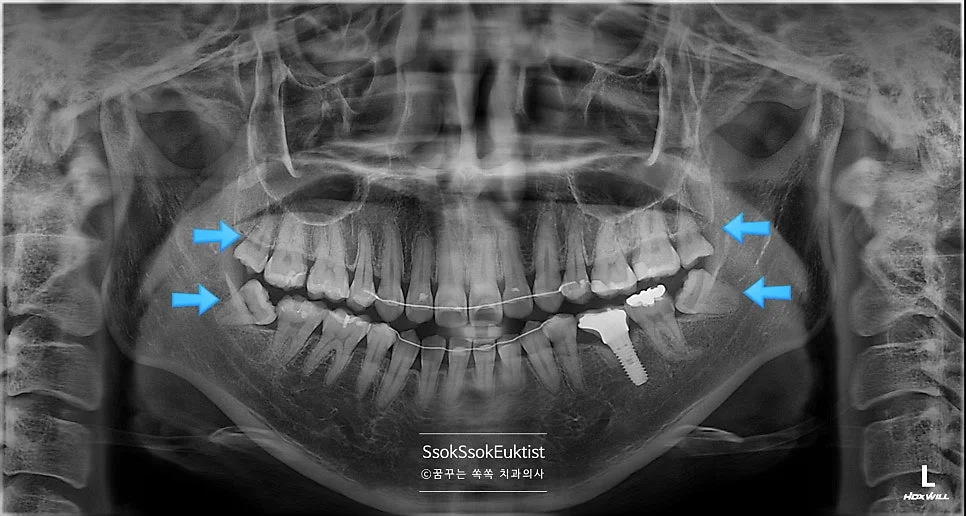

구강 전체 사랑니 4개 진단 사진

사랑니는 4개가 다 있고, 다 발치해야 하는 상황이네요^^

파란 화살표로 표시되어 있는 치아가 사랑니입니다! 위 사랑니는 크기가 좀 작지만 비교적 얌전히 나있는데요!

아래 두 개의 사랑니를 보면 머리부터 충치가 상당히 진행되어 있는 것을 볼 수 있습니다. 아래 사랑니는 매복 사랑니이기 때문에 발치를 해야 하고, 위 사랑니는 아래 사랑니를 제거하면 닿는 치아가 없어 필요 없고 관리만 안 되는 사랑니이기에 발치를 하는 것을 추천합니다!^^